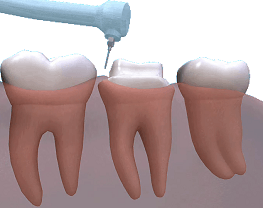

Cfare jane kellefet dentar?

Kellefet jane kurora artificiale ne formen e dhembit.Ato vendosen mbi dhembin e preparuar (ose kultin ),per ta mbrojtur ate dhe per te permiresuar anen estetike .

Kur jane te nevojshme kellefet dentar?

Per te mbrojtur nje dhemb te dobet (psh qe ka qene shume i prishur )dhe ka mbushje masive

Riparimin e nje dhembi te thyer

Si pjese perberese e urave

Per mbulimin e implantit

Per mbulimi e nje dhembi qe ka ndryshuar ngjyre ose ka forme jo estetike

Per te bere modifikime estetike